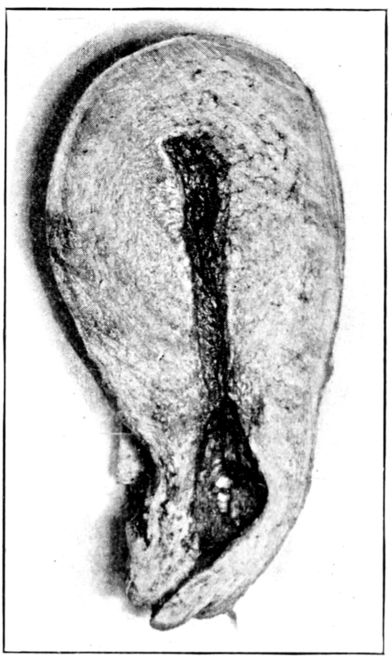

23. Maternal surface of the placenta 74

24. Fetal surface of the placenta 75